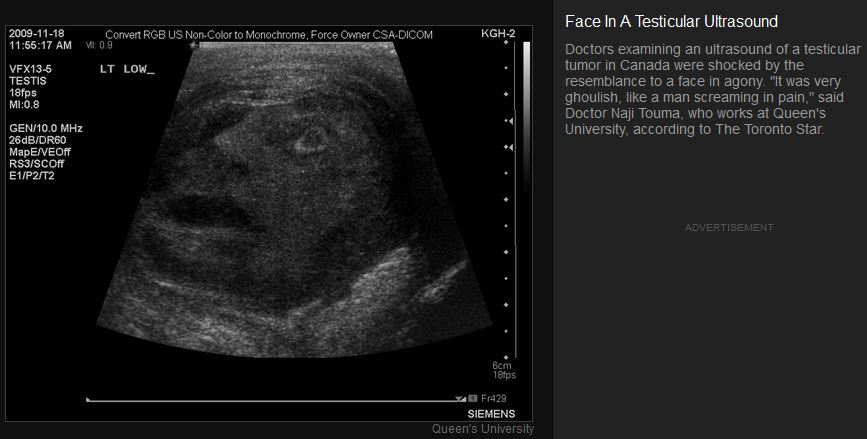

1 Attachment(s)

Check out the face on some guys nutsack tumor:

Attachment 52744